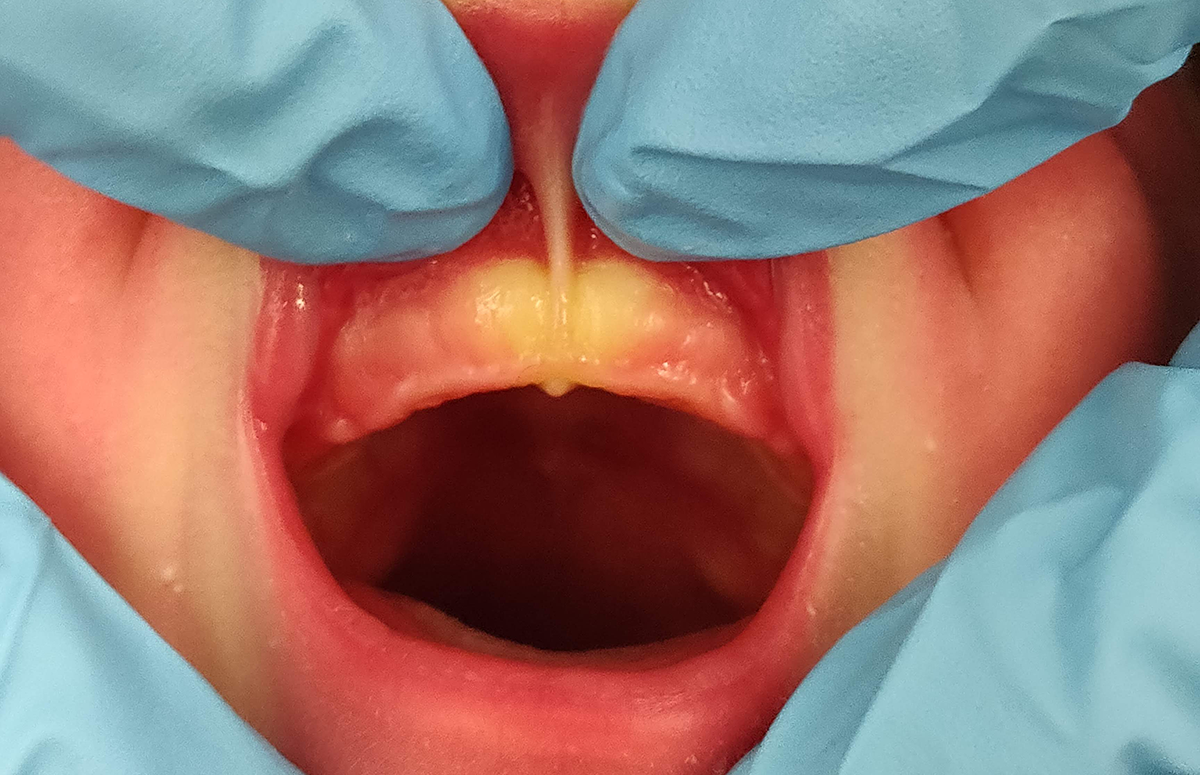

5. Ein Blanchieren (Blanching), also die Weißfärbung des Zahnfleisches am Ansatzpunkt ohne eine Funktionseinschränkung der Oberlippe, ist ein Faktor und kein allein entscheidender Grund, eine sublabiale Faszienplastik zur Optimierung des Stillens zu empfehlen, weil ein Blanchieren auch bei ausreichend guter Lippenfunktion auftreten kann (Abb. 1).

6. Eine Einkerbung (Notch) inmitten der Zahnleiste am Ansatzpunkt des Lippenbandes ist kein Hinweis dafür, dass dadurch das Stillen behindert wird (Abb. 2). Allerdings kann eine Einkerbung ein Hinweis dafür sein, dass die Kauleiste durch das Lippenband in der Entwicklung beeinträchtigt und deformiert wird (Abb. 3) und die Wahrscheinlichkeit für eine Lückenbildung bei den Frontzähnen erhöht sein könnte. Ein wissenschaftlicher Nachweis für diese Annahme fehlt noch. Heo [5] berichtet in einer Fallstudie von einer starken Verkürzung des Oberlippenbandes, die eine Hypoplasie des Prämaxillarbereichs, eine abnorme Lippenbewegung und -kontur bei einem Kind zeigt. Es bestand eine knöcherne anteriore Alveolarhypoplasie mit tiefem Sulkus im vorderen Oberkiefer, die mit einer 3D-Aufnahme mittels Computertomographie dokumentiert wurde. Ein postoperatives dreidimensionales CT-Bild des Gesichts, 10 Monate nach Frenotomie, zeigt ein gut knöchernes Wachstum von Prämaxilla und Alveole im Vergleich zum präoperativen CT-Status [5].